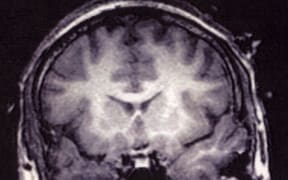

Suspicious minds

Guilt or innocence could soon be determined by brain wave technology, a New Zealand professor says. Audio